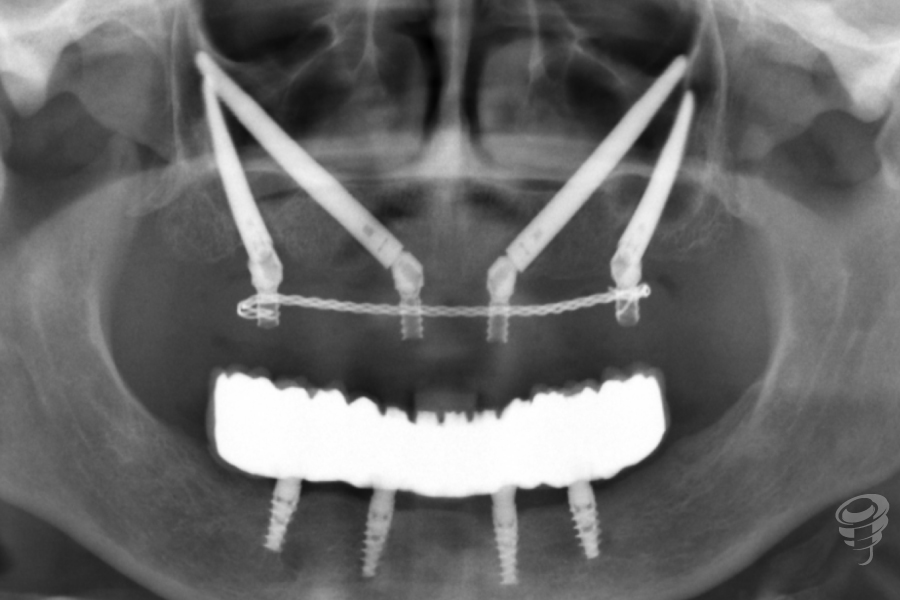

Protocolo Quad Zygoma. (Imagen 26-37)

Por otra parte, el Quad Zygoma nos pemite tratar maxilares con atrofia severa, con posibilidad de carga inmediata, ubicando los implantes en posiciones prostodóncicamente adecuadas que permiten una rehabilitación y mantenimiento convencionales, siendo muy importante para esta técnica evaluar la disponibilidad ósea del cuerpo del cigoma para alojar dos implantes.

Imagen 35 – Orto Postoperatorio Inmediato

Imagen 36 – Prótesis Definitiva (3 años)

Imagen 37 – Orto seguimiento (3 años)